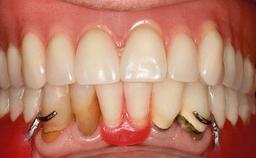

An 83-year-old man presented together with his caregiver at the dental department of the Medical University of Innsbruck, Austria with complaints of swelling in the right maxillary canine area and loss of retention of his 5-years-old mandibular denture. The patient had a significant medical history (20 years) of bipolar affective disorder with moderate depression (F 31.3) and dementia in Alzheimer’s disease (F 00.2). The patient had been in ambulant psychiatric therapy for his depressive illness for the past 20 years. He lived alone and had no children; his sister assisted with daily living. She reported that the patient exhibited compulsive hoarding behavior. In the previous two months, she had noted increasing disorientation and vertigo in the patient. She therefore accompanied him for a medical consultation at the Department of Psychiatry and Psychotherapy of the Medical University of Innsbruck. He was released home after a 6-week inpatient stay.